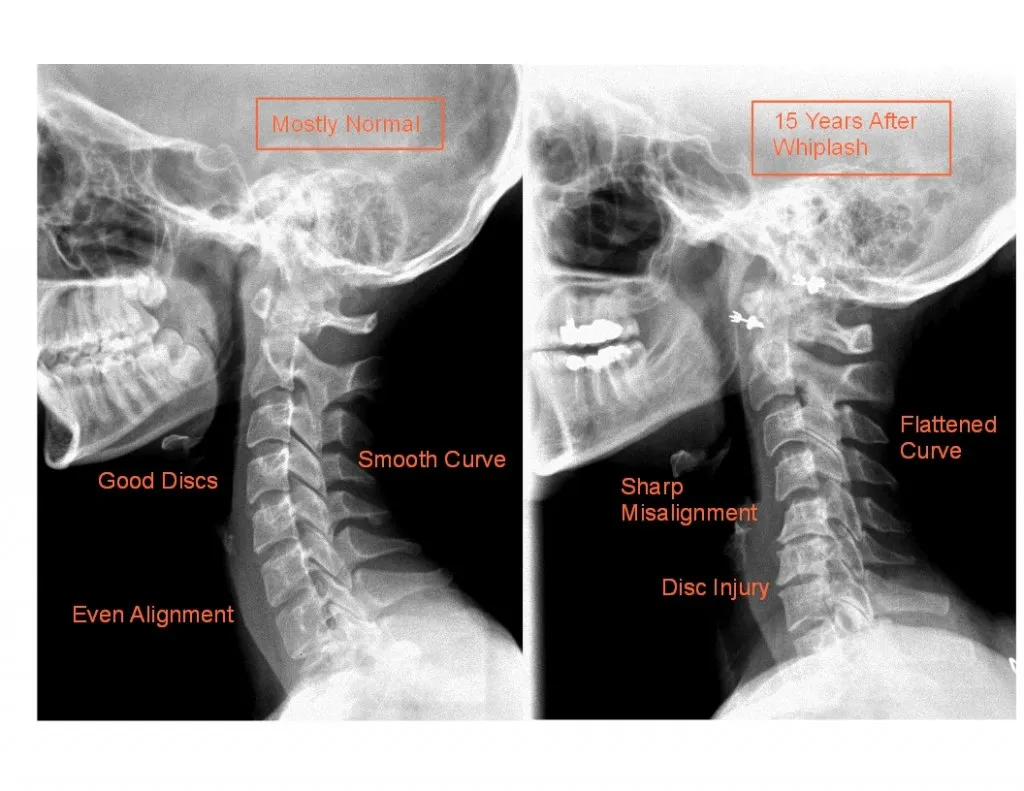

Skręcenie kręgosłupa szyjnego, znane również jako uraz "whiplash", może prowadzić do długofalowych skutków neurologicznych, które znacząco wpływają na codzienne życie pacjentów. Wiele osób doświadcza problemów z koordynacją oraz równowagą, co może prowadzić do trudności w wykonywaniu prostych czynności. Takie objawy mogą być wynikiem uszkodzenia nerwów lub mięśni, co z kolei wpływa na zdolność do poruszania się i utrzymania równowagi. Właściwe zrozumienie tych konsekwencji jest kluczowe dla osób, które doświadczyły urazu, aby mogły one dostosować swoje życie do nowych realiów.